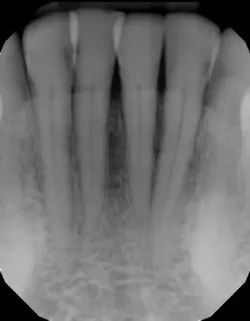

In another example, a young patient had been using e-cigarettes for five years. He started vaping as a method to quit smoking traditional tobacco products thinking vaping was a healthy alternative. Because of its ease of use, he smoked a cartridge of one of the more popular vaping products a day. Admittedly, he also drank energy drinks (high sugar content), stating that his mouth was often dry after vaping. This combination led to rampant decay with smooth-surface lesions and future tooth loss (figure 3).

Figure 3: Effects of e-cigarettes